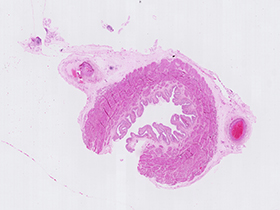

Uréter (tinción H&E)